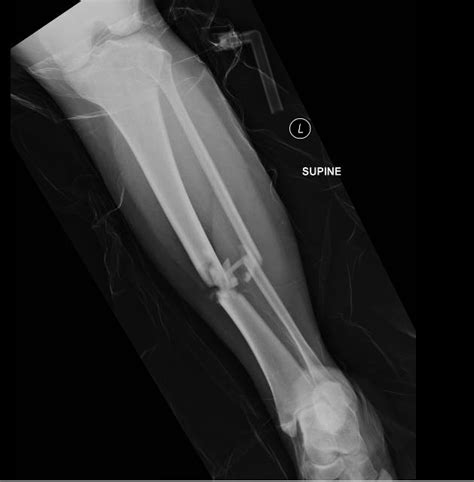

• Imaging Tests: X-rays are the primary imaging tool used to confirm a Tib Fib Fracture. In some cases, additional tests such as CT scans or MRIs may be required for a more detailed view of the fracture.

• Open Reduction and Internal Fixation (ORIF): The bone is realigned and held in place with plates, screws, or rods.

• Intramedullary Nailing: A rod is inserted into the marrow cavity of the bone to stabilize the fracture.

• External Fixation: Pins or screws are inserted into the bone and connected to an external frame to stabilize the fracture.